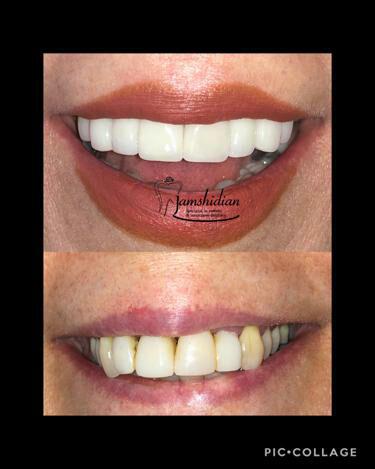

۱. ونیر کامپوزیت و سرامیکی

هر دوی این روش ها برای اصلاح رنگ، فرم و فاصله های بین دندان ها به کار می روند. با کمک ونیرها، دیگر نیازی به درمان های طولانی مدت ارتودنسی نیست. ونیر کامپوزیت و لمینت سرامیکی می توانند لبخندی کاملاً هماهنگ، طبیعی و درخشان برای شما بسازند و ظاهر دندان هایتان را به شکل چشمگیری بهبود ببخشند. آن ها همچون یک پوشش نازک و زیبا روی سطح دندان ها قرار می گیرند و نقص ها را می پوشانند.